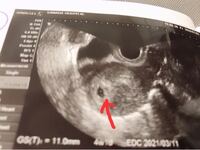

胎嚢確認ができる時期はいつ? 早い人は、妊娠4周ごろ から確認できます。 通常であれば、 遅くとも6週まで には確認できるようになります。5w6d 初診・胎嚢確認(※最終生理日からの計算です) いつ初診に行く? 初診をいつにしようか悩みましたが、 ほぼ確実に胎嚢が確認でき、また万が一 子宮外妊娠でも遅すぎない時期・・・ と思って、 最終生理開始日から5w6dの日に初診を受ける ことにしました。 会社でのお勤め終了後、旦那 胎嚢は最短でいつ確認できますか 避妊 19 何日後から妊娠検査薬が反応するか。 妊娠 エコー写真出ます 妊娠10週です 頭のところが二箇所黒い丸になってるのはなぜですか? 妊娠 関連するQ&A 1 妊娠5w6dの尿中hcgについて教えて下さい。 4w6dで胎嚢が確認出来ず、今日5w6dで胎嚢のみ確 2 15

産婦人科医監修 胎嚢 たいのう の大きさの平均は 妊娠5週 6週 7週の目安は 週数別に解説 ままのて

胎嚢が小さい原因は 妊娠5週や6週の平均的なサイズは こそだてハック

胎嚢の大きさの平均ってどれくらいなの ママリ